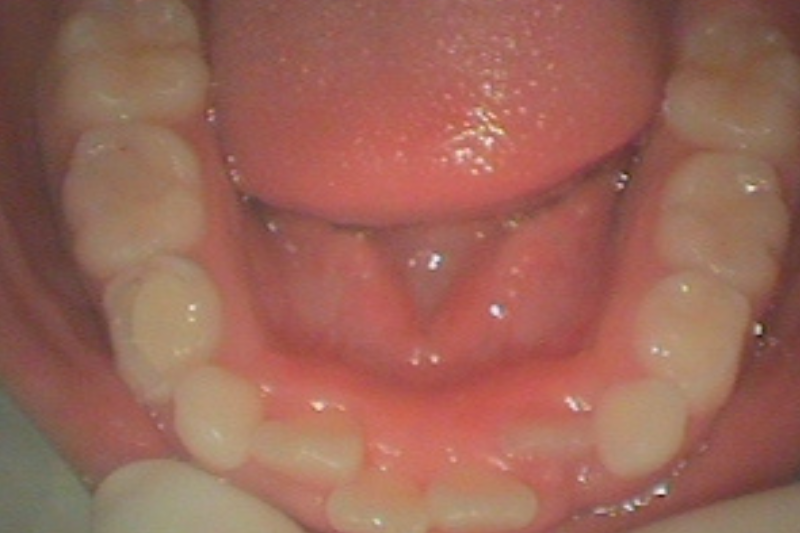

治療例(前歯・反対咬合)

下記の図を見ていただくとわかる通り、下の前歯が反対咬合(はんたいこうごう)になっています。

これから生えてくる永久歯の生える場所がありません。 矯正装置のプレートを使用して、顎を少し拡げます。

永久歯の生えてくる場所をつくることができ、前歯のかみ合わせが治ります。

プレートをよく使用していただいたので、非常に美しい歯並びになります。

dogs

治療後の現在は虫歯もなく、きれいで美しい状態を保っています。

定期的に診ていくとき同時に、歯のおそうじと虫歯にならないよう予防をしています。